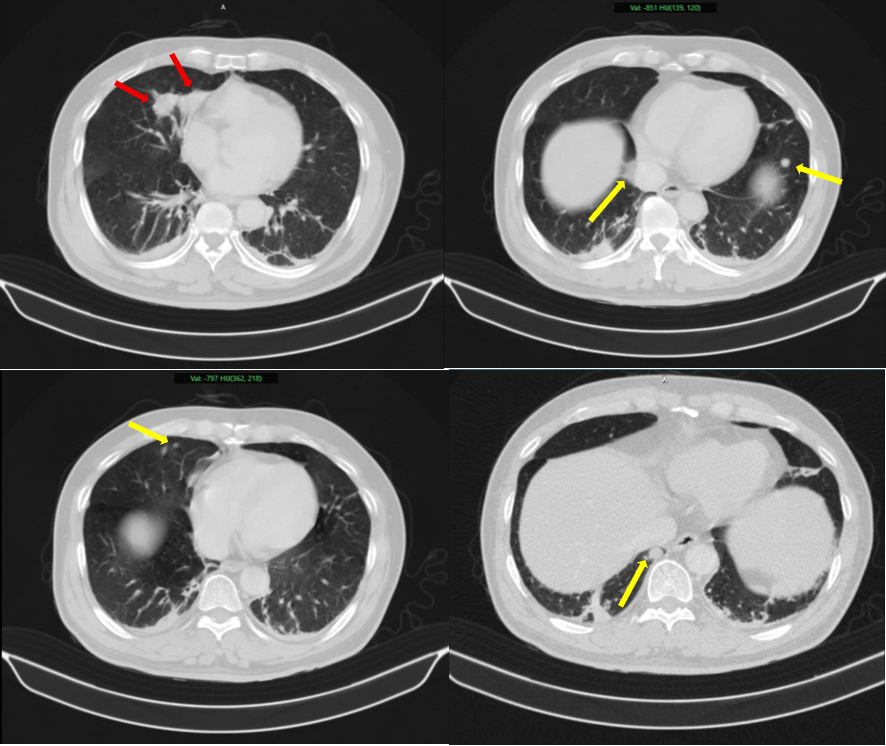

Hình ảnh 02 khối u bờ đa cung ở nhu mô thùy giữa phổi phải, dính vào màng phổi trung thất (mũi tên đỏ) kèm nhiều nốt đặc nhỏ rải rác nhu mô phổi hai bên (mũi tên vàng) gợi ý tổn thương thứ phát.

Trong thực tế, khi xuất hiện nhiều khối u ở các cơ quan khác nhau, phần lớn trường hợp là ung thư di căn. Nếu chẩn đoán sai nhầm lẫn giữa u nguyên phát và tổn thương thứ phát phác đồ điều trị sẽ bị lệch hướng, ảnh hưởng trực tiếp đến tiên lượng sống của bệnh nhân.